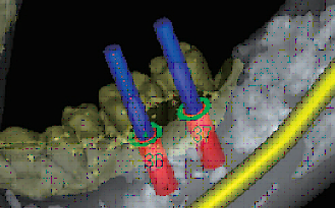

BioNaシミュレーション画像

BioNaシミュレーション画像 歯牙支持型フラップレス

歯牙支持型フラップレス